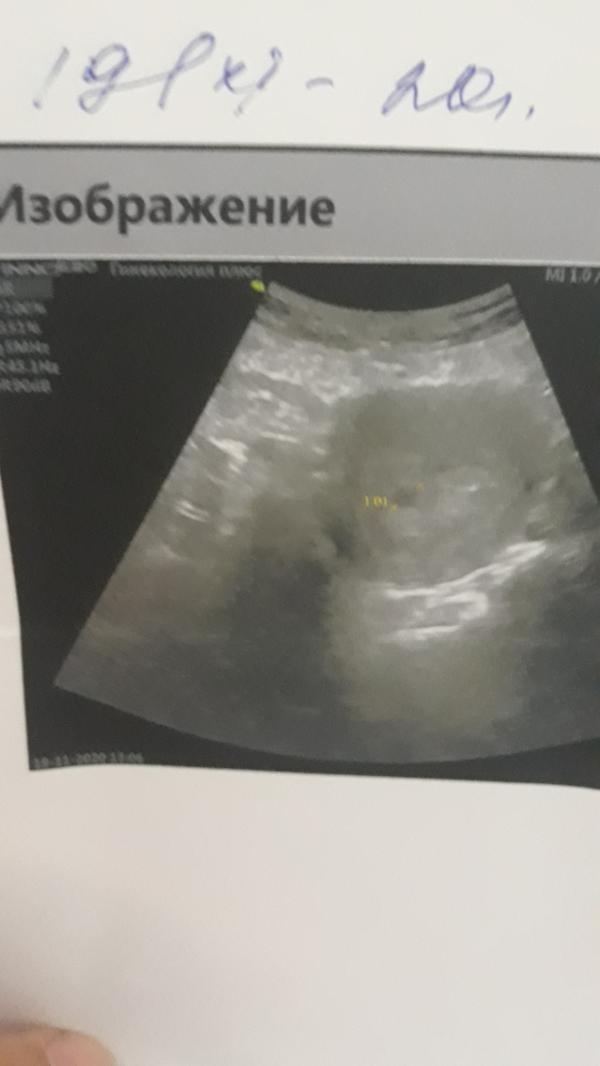

Срок маленький только 2-3 недели сказали прерывать по состоянию здоровья